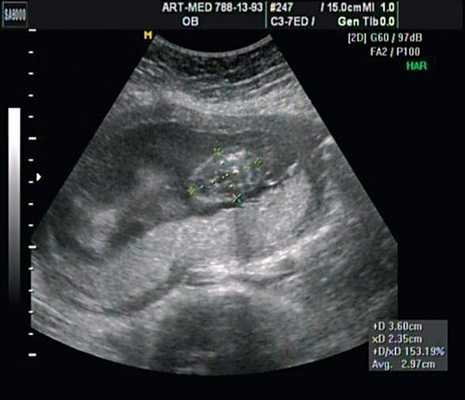

При эхокардиографии изучались четырехкамерный срез сердца плода (рис. 1) и срез через три сосуда (рис. 2). УЗИ проводилось трансабдоминальным датчиком, лишь при необходимости (затрудненная визуализация) использовался внутриполостной датчик. Четырехкамерный срез сердца плода при ультразвуковом сканировании трансабдоминальным датчиком визуализировался в 85% случаев, срез через сосуды - в 73%, при использовании трансвагинального датчика эти цифры существенно возрастали до 100 и 91% соответственно. Оптимизация пренатальной диагностики ВПС может быть достигнута путем строгого соблюдения основных методических правил. При оценке четырехкамерного среза плода необходимо оценить нормальное расположение сердца плода, исключив его эктопию (рис. 3), положение оси сердца плода, что не представляет никаких трудностей, нормальные пропорции и размеры камер сердца, движение створок атриовентрикулярных клапанов должно быть свободным, септальная створка трикуспидального клапана должна располагаться ближе к верхушке сердца (рис. 4). При оценке среза через три сосуда необходимо оценить взаиморасположение сосудов и их диаметр.

Рис. 1. Беременность 12 недель. Четырехкамерный срез сердца плода. Отчетливо видны камеры сердца.